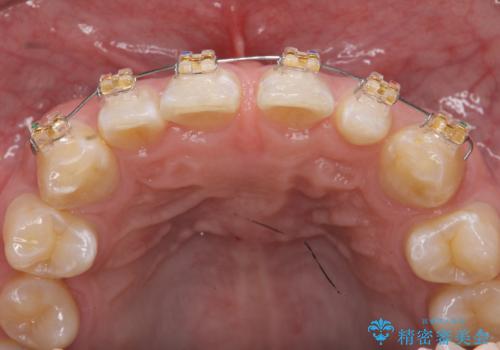

- 上顎前歯のすきっ歯が気になるといらっしゃった方の症例です。

上顎前歯のみの治療を希望されたので、部分矯正を行いました。

左上2の矮小歯はオールセラミッククラウンによる補綴を行いました。